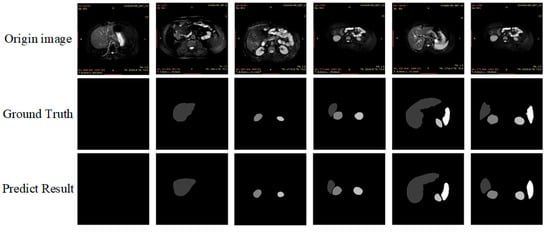

As can be seen in Table 6, the mIoU and mPA values of the ResNet50 backbone PSPNet network are 81.04% and 89.66%, respectively, lower than the algorithm in this paper by 1.28% and 0.44%, respectively. While the mIoU values of PSPNet and Deeplabv3+ networks using MobileNetV2 [53] backbones are 76.41% and 75.92%, which were lower than the algorithm in this paper by 5.92% and 6.41%, respectively. The mPA values were 87.02% and 86.04%, lower than the algorithm in this paper by 3.08% and 4.06%, respectively. We also found some dedicated algorithms for MRI 2d images for comparison. mIoU and mPA values for M-FCN are 77.21 and 86.40, respectively—5.12% and 3.7% lower than the algorithm in this paper. mIoU and mPA values for U-Net_based are 77.86 and 85.14, respectively, 4.47% and 4.96%, lower than the algorithm in this paper, respectively. The prediction plots of organ segmentation for each algorithm are shown in Figure 11.

Figure 11.

The prediction plots of organ segmentation for each algorithm.

As shown in Figure 11 above, based on visual observation, the algorithm in this paper is closest to the gold standard in terms of organ edge structure, and there are no organ prediction errors and more well-defined angles.

However, at the same time, we observed segmentation errors in the above VGG prediction result maps and PSPNet, and MobileNetV2 backbone prediction images, which all showed incorrect predictions of liver images in the third set of image predictions, of which we analyzed the reasons as follows: